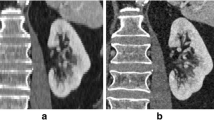

The least realistic imaging setup is scanning artificial models in air, while the most realistic one involves scanning real patients for a clinical assessment (Fig. 11).

George et al. noted that the deviation of the segmentation process may be significantly lower when the original structures are scanned in air compared to in situ image acquisition [67]. This can pose a challenge: The most realistic imaging setup can only be combined with the least accurate measurement method. Therefore, a viable compromise is desirable. Cadaver studies have frequently been employed for this purpose as gold-standard [15, 69, 74]. These involve the dissection of soft tissue before or after imaging to allow reference measurements on the target structure of the segmentation (original structure). However, cadaver studies are expensive, personnel-intensive and need ethical approval in advance.

An accurate and realistic assessment of SegE can generally be defined as follows: A complex three-dimensional (anatomical) structure is surrounded by randomly arranged isodense structures during imaging. It is then segmented, and a 3D-scan of the original structure is compared with the direct segmentation result via surface comparison. Based on this definition, cadaver studies may not be the optimal method to evaluate SegE, considering the enormous efforts. To overcome these obstacles, future endeavours could focus on developing simple segmentation models that use artificial (3D-printed anatomical) structures and simulate adjacent (soft-) tissue.

As a consequence, the need for alternatives seems justified. The combination of an artificial original structure with simulated adjacent tissue could be a promising solution that can be expected to achieve comparable accuracy and realism to cadaver studies but with significantly reduced cost and effort. Some attempts have been described in the literature to simulate adjacent tissue to increase the realism of the segmentation process [77, 156]. However, those still involve the use of cadaveric specimens: Van Eijnatten et al. embedded a human dry skull in silicone to simulate soft tissue for validating the influence of the head position during cone-beam CT [156]. Zhang et al. [77] placed artificial models of nasal airways inside a dry skull to use them as a realistic benchmark for the validation of their segmentation algorithm.